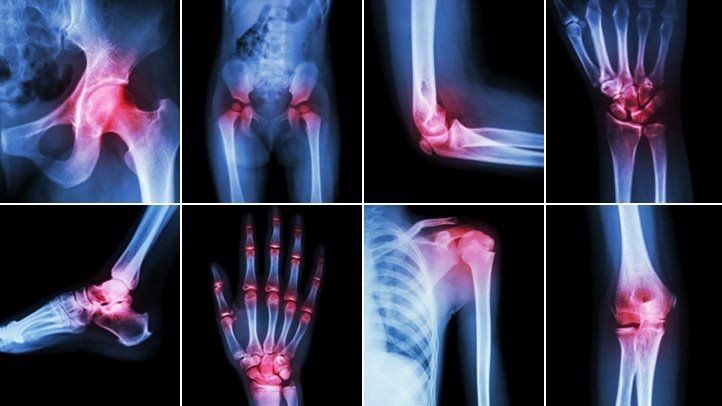

Joints form the connections between bones. They provide support and help you move. Any damage to the joints from disease or injury can interfere with your movement and cause a lot of pain.

Many different conditions can lead to painful joints, including osteoarthritis, rheumatoid arthritis, bursitis, gout, strains, sprains, and other injuries. Joint pain is extremely common. In one national survey, about one-third of adults reported having joint pain within the past 30 days. Knee pain was the most common complaint, followed by shoulder and hip pain, but joint pain can affect any part of your body, from your ankles and feet to your shoulders and hands. As you get older, painful joints become increasingly more common.